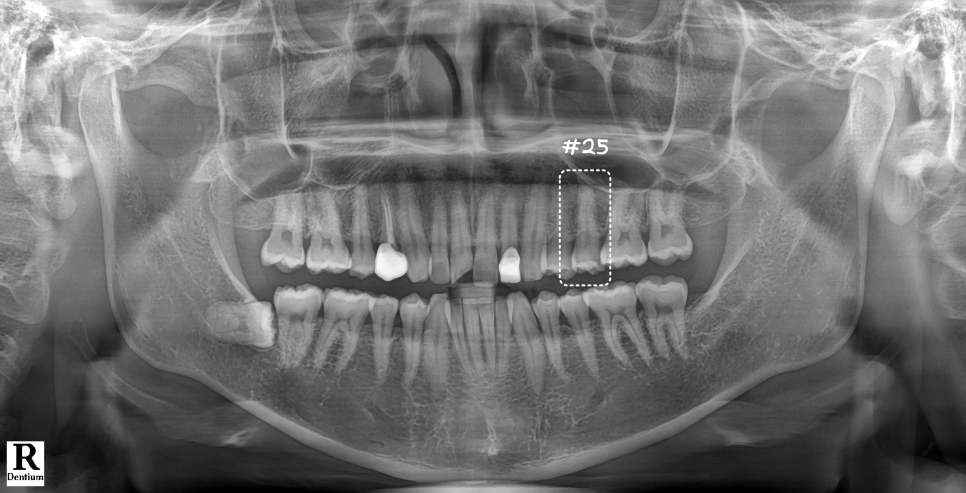

깊은 충치로 인해 신경이 살짝 노출되어 있었어요.

엑스레이로 확인했을 때도 다행히 아직 염증이 심하지 않았는데요. 그래서 신경치료 없이 레진으로 마무리하기로 했어요.